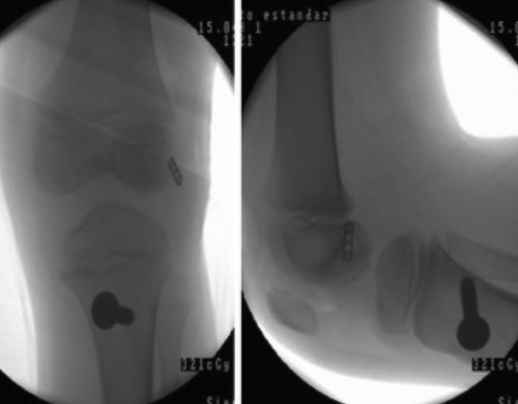

Figura 5. Radiografía de control intraoperatoria de un paciente de 6 años con reconstrucción según la técnica transepifisaria de Anderson.

Otra de las técnicas de ahorro fisario es la llamada all epiphyseal. La primera de estas técnicas fue descrita por Anderson(13)(Figura 4) y está indicada en pacientes en estadio de Tanner I, II o III. Se realiza evitando la invasión de la fisis por parte de los túneles, utilizando injerto cuadrifascicular de isquiotibiales, que son estabilizados en el fémur mediante un sistema de tenosuspensión cortical y en la tibia con un tornillo interferencial distal a la fisis (Figura 5). Los resultados en un grupo de 12 pacientes fueron buenos, pero refieren que la técnica es compleja y demandante para un cirujano no experto en rodilla. Esta técnica minimiza el daño fisario, es anatómica y reproduce la isométrica(71). Se ha descrito la aparición de una deformidad angular relacionada con una epifisiodesis secundaria por sobretensionado de la plastia. En la actualidad, se han descrito multitud de modificaciones de esta técnica(15,72,73,74)(Figura 6).